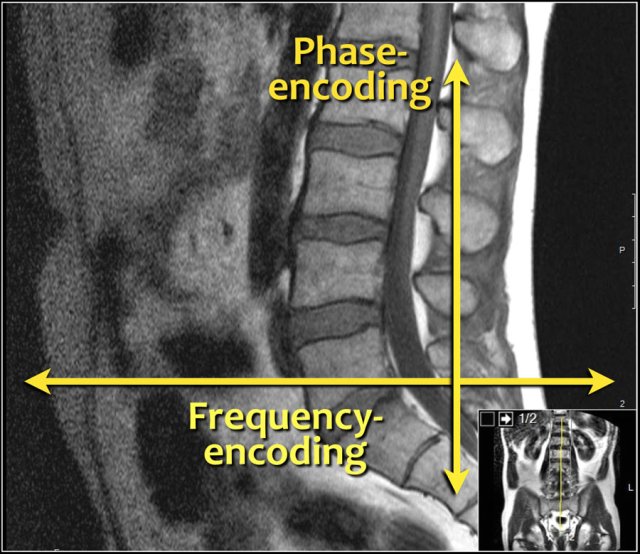

The frequency-encoding should be in the AP-direction and consequently the phase-encoding feet-head.

This has several advantages:

1. The resolution is the highest in the frequency-encoded direction.

We want the highest resolution in the AP-direction to look for small herniations and delineation of nerve roots.

2. When you have the phase encoding in the AP-direction, you get breating artifacts. That is why some use a saturation band or the RFOV.

With the frequency-encoding in the AP-direction you do not have these problems and you do not need a saturation band.

3. Frequency encoding in the feet-head direction can result in poor deliniation of the vertebral endplates due to chemical shift artifact when the fat in the vertebral body meets the water in the disc.

This is another reason to use a feet-head phase encoding and an AP frequency encoding.